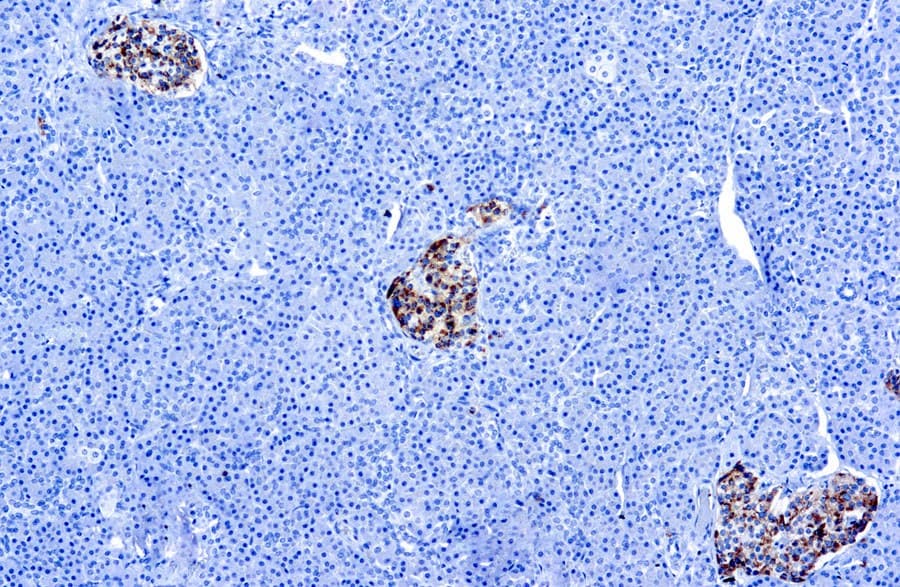

Na mucosa gastrointestinal normal, a CgA está presente em células endócrinas e é a principal proteína da família das graninas expressa em muitos tecidos neuroendócrinos. Estudos imuno-histoquímicos demonstraram uma coloração intensa de CgA em células endócrinas do estômago ao reto, destacando a sua ubiquidade entre as populações de células neuroendócrinas no trato digestivo. A expressão de CgA reflete a presença de grânulos de núcleo denso, que são caraterísticos da diferenciação neuroendócrina. Este atributo biológico sustenta o seu significado diagnóstico: a CgA permite a visualização e identificação de células de linhagem neuroendócrina e tumores em tecidos gastrointestinais que, de outra forma, poderiam ser indistinguíveis na histologia de rotina.

Em patologia gastrointestinal, a imuno-histoquímica para CgA é um marcador estabelecido para a diferenciação neuroendócrina e é rotineiramente incluída em painéis para caraterizar suspeitas de neoplasias neuroendócrinas (NENs). Os tumores neuroendócrinos (NETs) do sistema gastroenteropancreático demonstram frequentemente uma expressão robusta de CgA, o que auxilia na sua distinção de carcinomas não neuroendócrinos. A coloração de CgA é particularmente valiosa porque muitos NETs secretam CgA independentemente de síndromes hormonais, proporcionando sensibilidade na deteção de tumores tanto funcionais como não funcionais. No entanto, os padrões de expressão de CgA podem variar entre os subtipos tumorais: por exemplo, alguns carcinoides retais podem apresentar menor imunorreatividade para CgA, sublinhando a importância da seleção do anticorpo e de painéis de marcadores abrangentes.